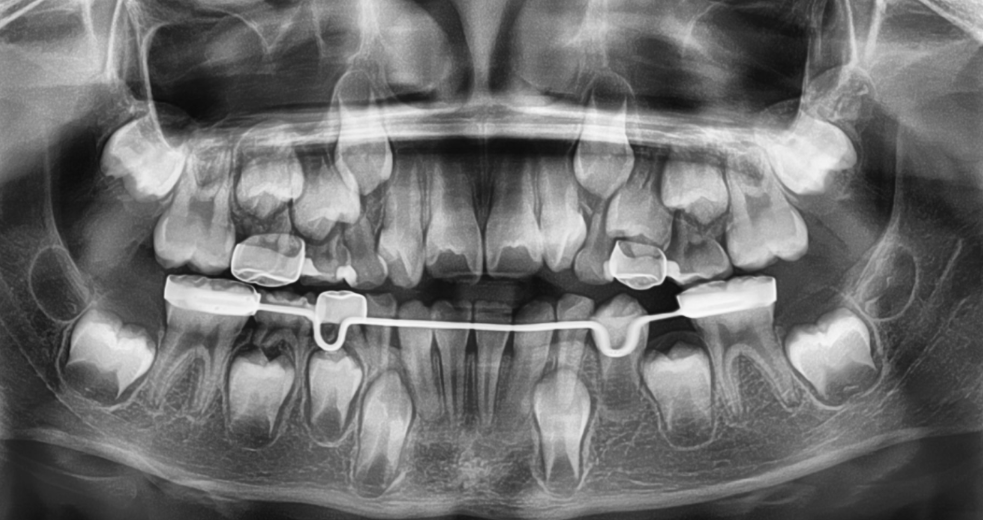

Panoramic dental X-ray showing teeth, roots, and braces wire in the lower jaw.

Mantenedores de espacio

Los mantenedores de espacio ayudan a conservar el espacio que queda cuando un diente de leche se pierde prematuramente, guiando a los dientes permanentes para que erupcionen en la posición correcta. Esto previene apiñamiento, desplazamientos y problemas ortodónticos más complejos en el futuro. Contar con una ortodoncista que supervise este proceso garantiza un diseño, ajuste y monitoreo precisos para obtener los mejores resultados a largo plazo.